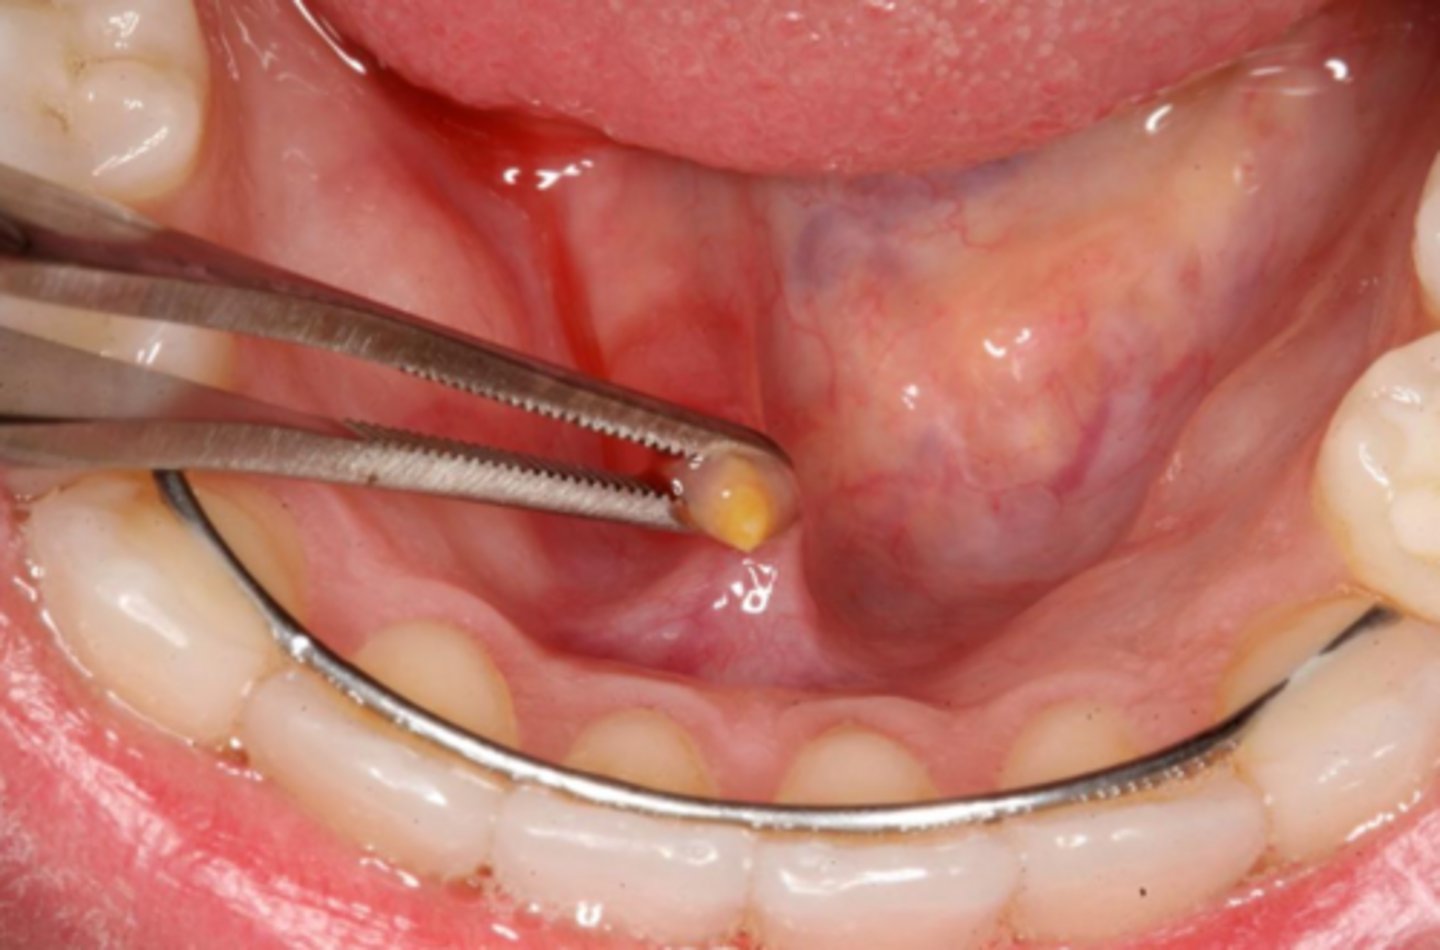

what is the calcified, round, yellow, hard mass structure within the salivary ductal system caused by the deposition of calcium salts around a nidus of debri within the lumen?

sialolith

what reactive salivary gland lesion most commonly occurs in the submandibular gland/duct due to the tortuous path of Wharton's duct and may be firm/hard?

sialolithiasis

how are small sialoliths treated? how are large sialoliths treated?

milking the stone out; need surgical removal (entire gland may need to be removed)

what reactive salivary gland lesion is treated with sialagogues, moist heat, and fluid intake to promote passage?